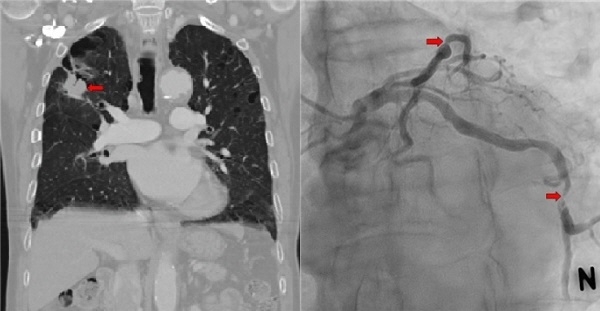

세종시에 거주하다 보니 수술을 위해 지난 8월 10일 세종충남대병원에 내원했고 이튿날 수술 전 시행한 검사에서 심혈관의 삼중 혈관 질환이 발견됐다.

삼중 혈관 질환은 스텐트 시술이 어렵고 시술이 이뤄지더라도 이중항혈소판제재를 복용해야 하는 기간 탓에 폐암 수술이 6주 정도 지연돼 폐암의 진행 가능성이 크다.

또 다른 문제는 삼중 혈관 질환에 대한 치료 없이 폐암 수술을 할 경우 수술 중이나 수술 이후 심근경색의 위험도가 높아 심혈관 질환에 대한 치료가 선행돼야 한다.

세종충남대병원 흉부외과 조현진 교수(흉부종양)와 한우식 교수(심장혈관)는 8월 14일 관련 분과의 협진을 통해 무펌프 관상동맥 우회술에 이은 폐엽 절제술 및 종격동 림프절 절제술을 동시에 진행했다.